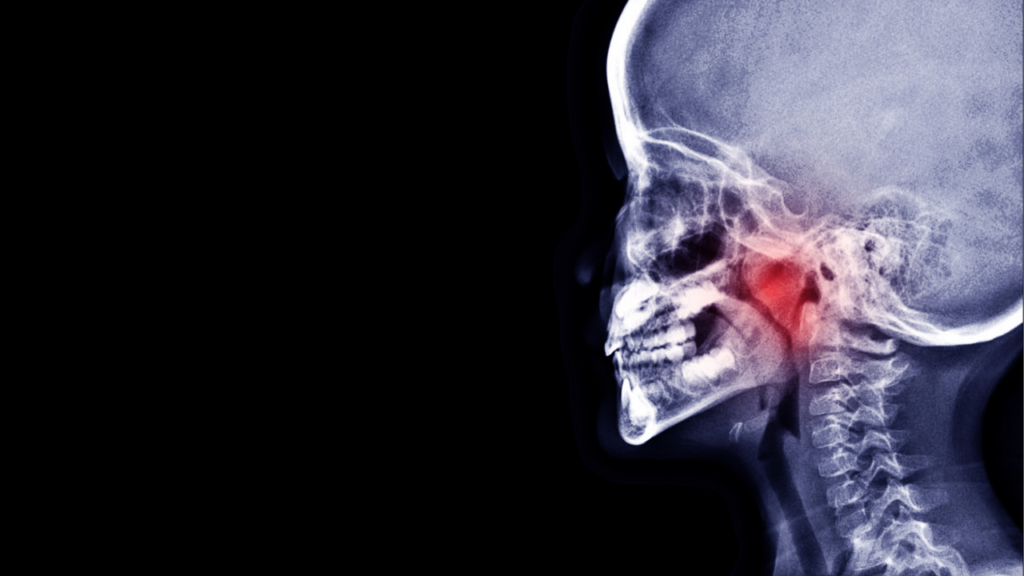

上咽頭炎とは?

「上咽頭」とは鼻の奥にある空間で、空気中のウイルスや細菌をブロックする免疫器官の役割を果たします。

しかし、ホコリやアレルゲンの影響を受けやすく、炎症が慢性化しやすい場所でもあります。